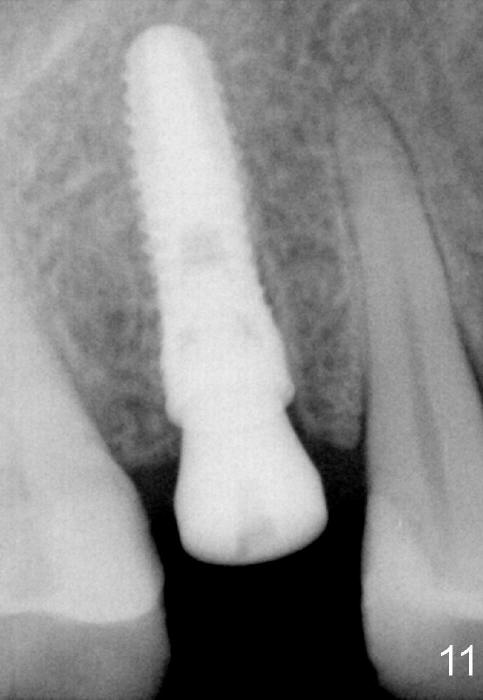

There is no abnormality around the implant 2 months postop (Fig.11).